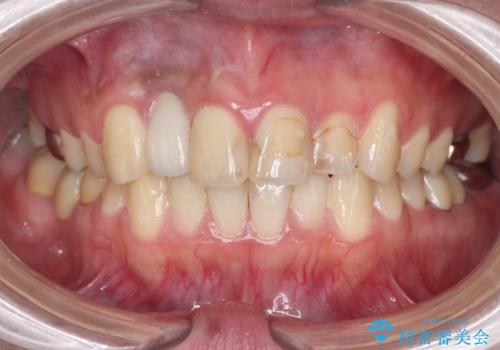

- 虫歯の治療を繰り返した前歯の見た目の改善を求めて来院されました。

大きく詰められたコンポジットレジンと虫歯の再発が見られ、経年劣化により審美性も損なわれていました。

充填されたコンポジットレジン・再発した虫歯を神経に影響が出ないよう丁寧に除去し再充填をしたのちオールセラミッククラウンで前歯の審美性を回復します。

※右上2のインプラント治療は他院のものです。